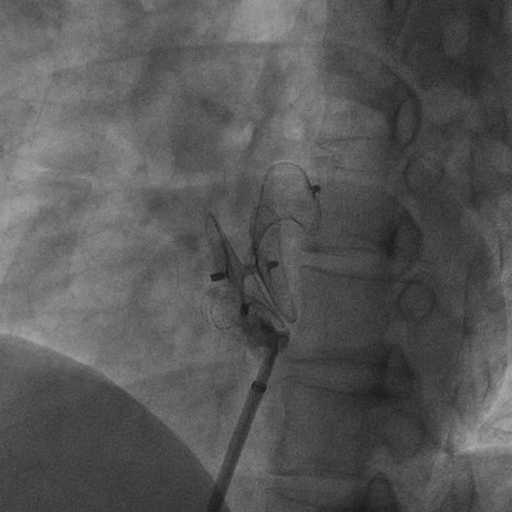

在獲得患者同意后,1月12日,尚福軍主任為患者進行了PFO封堵術。術中造影可見封堵器殘余漏,尚福軍主任用精湛的技藝,順利通過封堵器殘余漏裂縫,將右心導管從右房送入左房,且順利到達肺靜脈;遂行卵圓孔未閉封堵術后殘余漏再次封堵;且完美釋放PFO封堵器,可見兩封堵器呈“馬蹄蓮”狀,再次術中造影未見殘余漏。